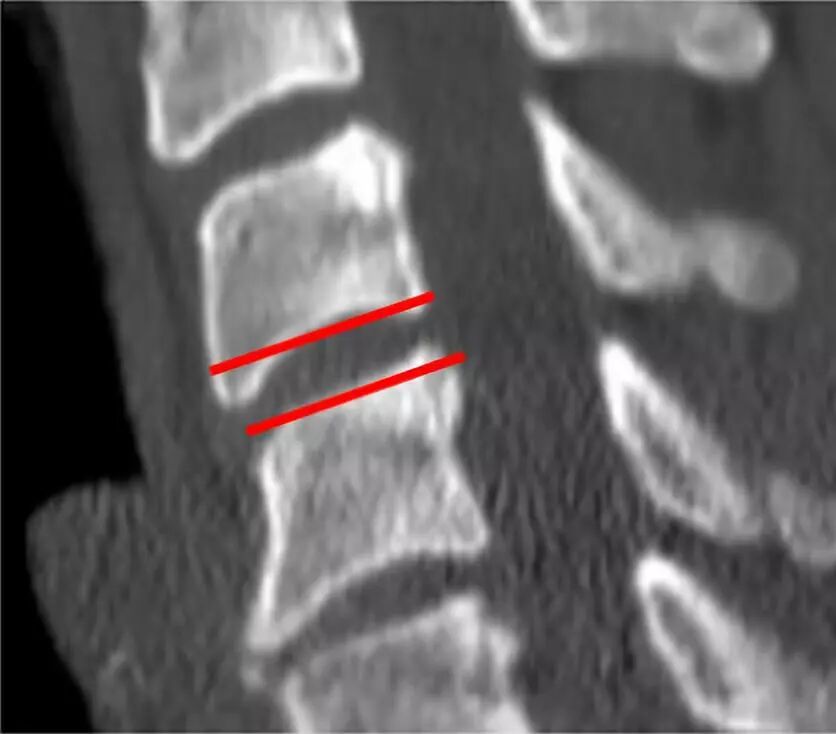

去除前部和后部骨赘(头侧和尾侧)以形成用于插入椎间融合器的平行通道。

用刮匙和/或锉刀进行终板准备以增强椎间融合。

去除前部和后部骨赘将确保放置适当大小的融合器/植入物。

避免融合器/植入物过大。这可能导致破坏骨性终板并最终导致过度下沉。